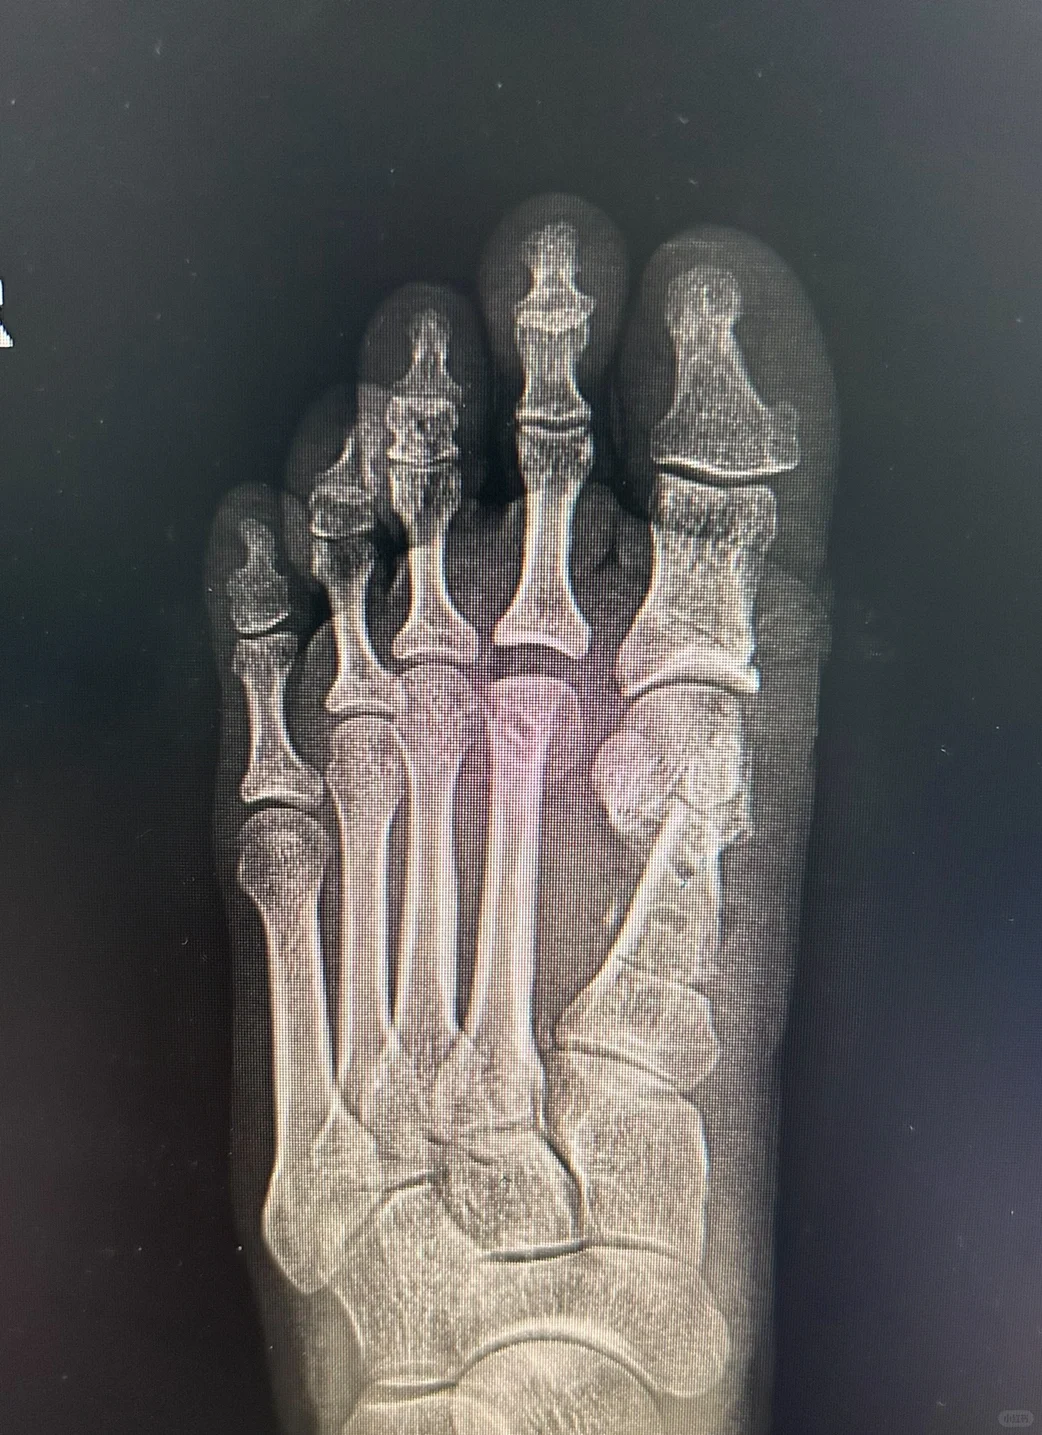

以前对于这种畸形的翻修都是原位断骨,哪来哪去的方法,两次在同一部位断骨,不仅血运损伤很重,拇趾会更短,而且断骨非常不稳定,很容易跑位置,不能在最佳的位置上稳定愈合。

经过多年研究,和大量微创术后患者的配合,我们成功研究出针对这种畸形的翻修方法。

可靠,接触面积大,术后可以下地负重。关节匹配良好。